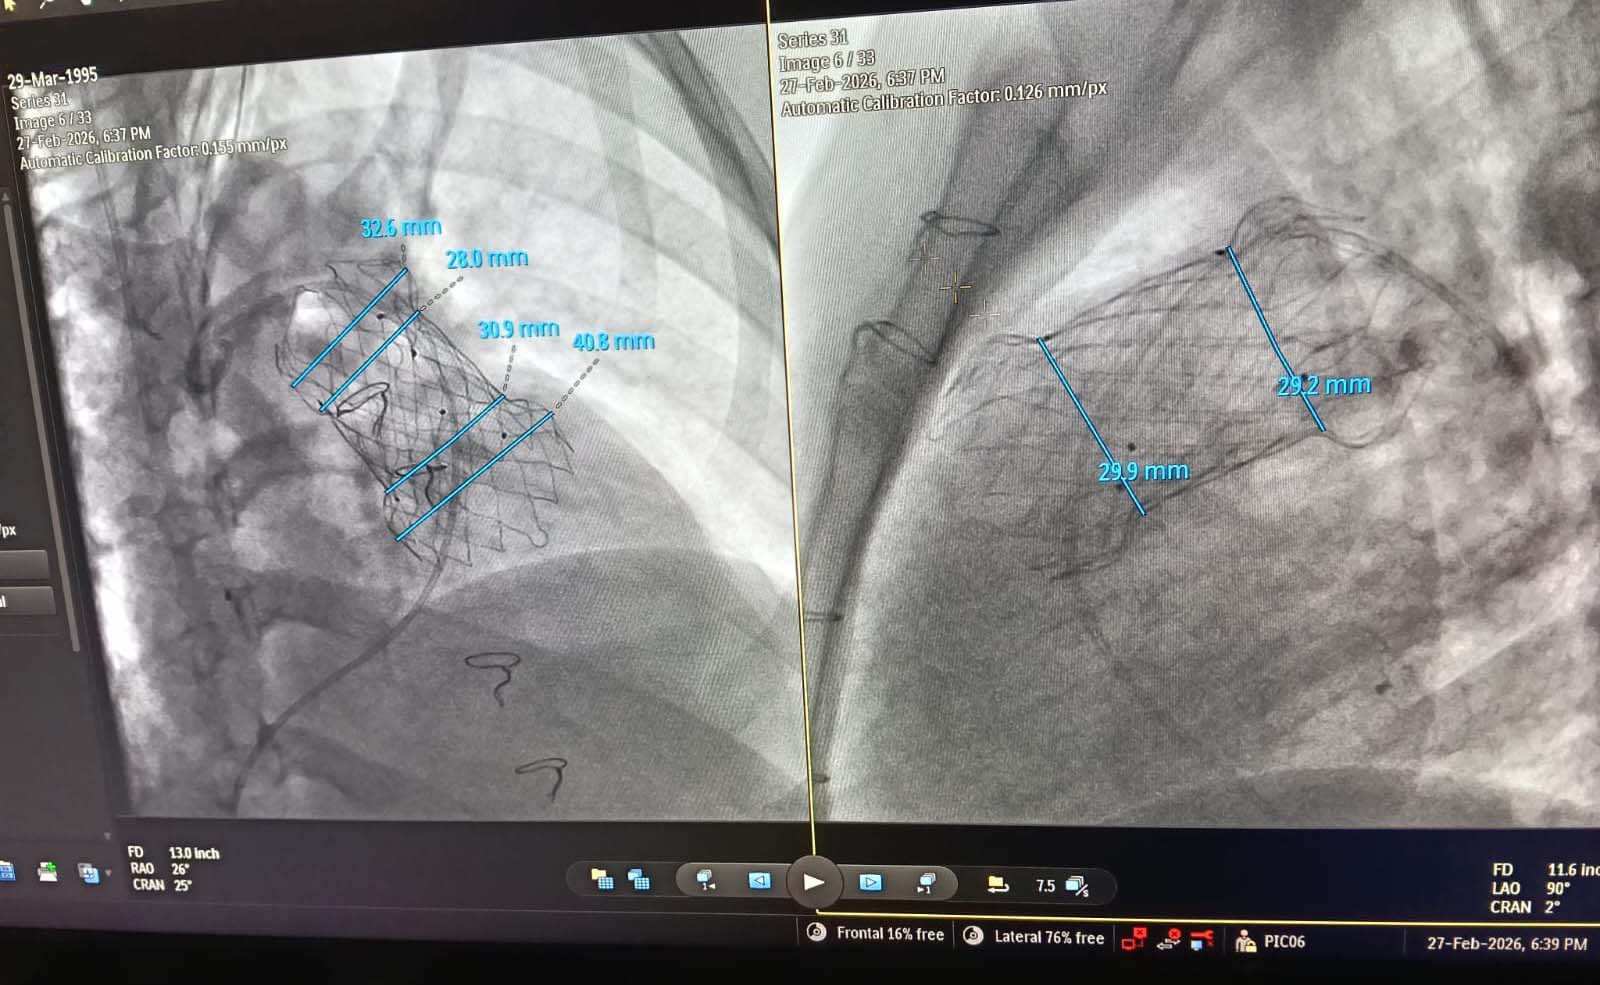

The Paediatric Cardiology team at Peshawar Institute of Cardiology (PIC-MTI), under the leadership of Prof. Ijaz Hussain, successfully performed transcatheter pulmonary valve implantation procedures in three patients. The procedures were conducted with the valuable support and supervision of a visiting team of paediatric cardiologists from Thailand,reflecting PIC’s commitment to international collaboration and clinical excellence. All patients recovered well following the procedures and have been safely discharged. PIC-MTI continues to provide advanced, high-end tertiary cardiac care services to the people of Pakistan. These achievements are made possible through the continued support of the Government of Khyber Pakhtunkhwa, ensuring timely funding and strengthening specialized healthcare services in the province.